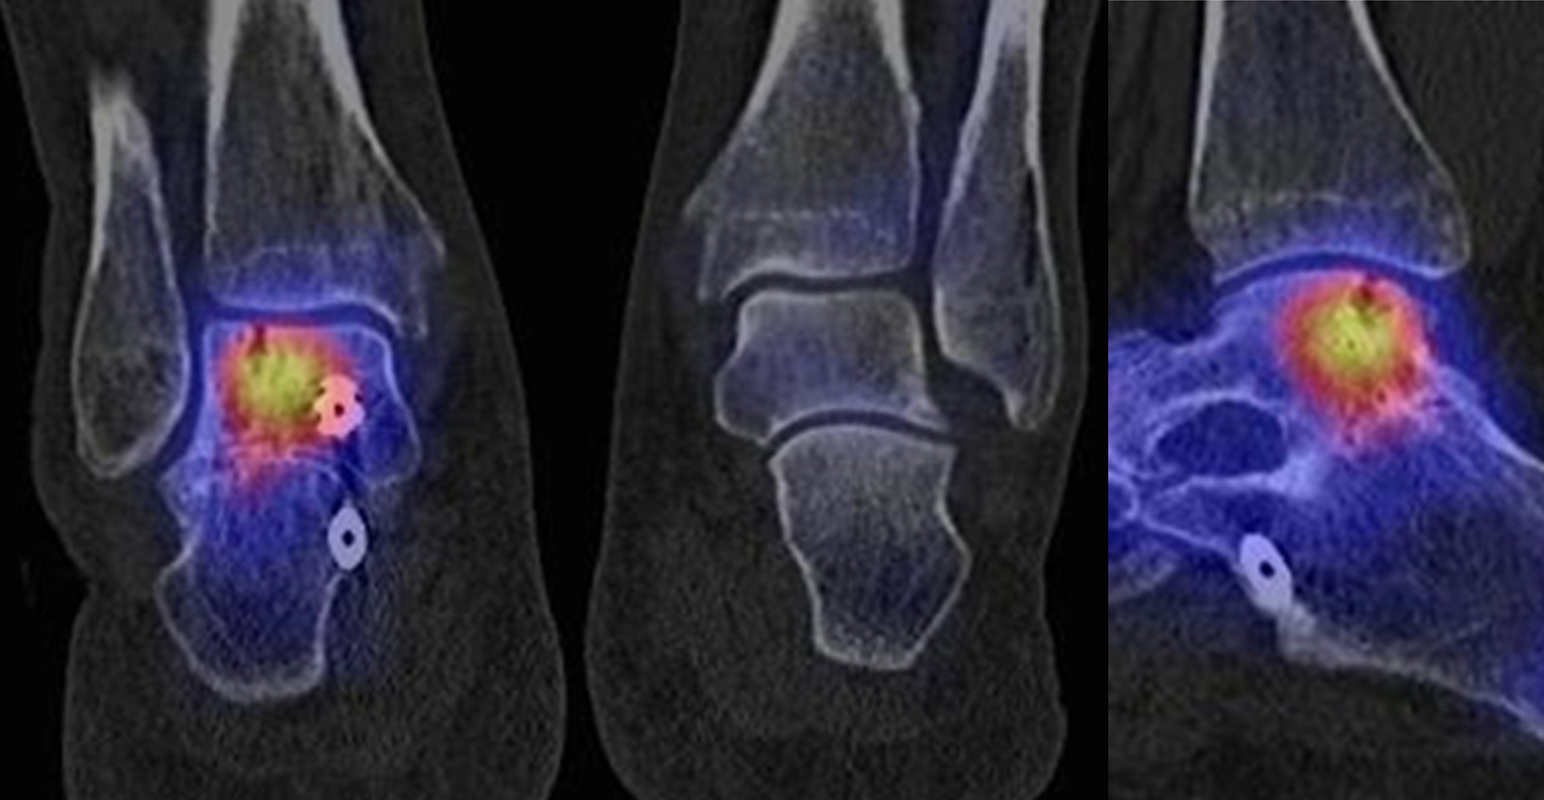

Abbildung 1.3.a und Abbildung 1.3.b: Der Patient hatte einen Skiunfall vor 40 Jahren mit distaler Tibiatrümmerfraktur. Nachfolgend Entwicklung einer Osteomyelitis; Operation mit Implantation eines Knochenspans. Klinisch rezidivierende Schwellungen des oberen Sprunggelenkes, bekannte Tibiafehlstellung. Frage nach Osteomyelitis, Status der Arthrose. Man sieht in Abbildung 1.3.a in der distalen Tibiametaphyse im CT Strukturveränderungen, die zu einer abgelaufenen Osteomyelitis passen - szintigraphisch hier keinerlei Anreicherungen und somit kein Infektverdacht, jedoch Nachweis einer aktivierten oberen und unteren Sprunggelenksarthrose.

Zum Lesen der Bildbeschreibung und zur Vollansicht bitte die Bilder anklicken. Bilder: H. C. Rischke

Abbildung 1.4.a und Abbildung 1.4.b: Klinisch Verdacht auf talonaviculare Anschlussarthrose links bei Z. n. Fraktur im Bereich des linken Sprunggelenkes vor 17 Jahren. und Z. n. Oberschenkel-Unterschenkelfraktur vor über 40 Jahren. Obwohl auch CT-morphologisch im OSG arthrotische Veränderungen bestehen, ist nur die Arthrose im USG metabolisch aktiv bzw. als Ursache der Schmerzen einzustufen. Im Bereich des Talonavicular-Gelenkes - entgegen der klinischen Verdachtsdiagnose - kein erhöhter Metabolismus.